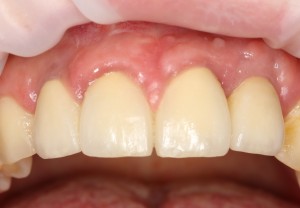

К счастью, уже через 6 недель после операции вдруг выяснилось, что ничего исправлять не нужно:

Фактически, нам осталось лишь дождаться приемлемого уровня остеоинтеграции имплантатов,  — примерно 2-3 месяца, — и можно переходить к постоянному протезированию.

Через три месяца мы сняли коронки с имплантатов, чтобы оценить качество формирования десневого контура:

С этого момента можно перестать переживать — десневой контур сформировался правильно, мы получили достаточный объём и качество окружающей платформу имплантата десны. Можно приступать к изготовлению постоянной протетики. Подрядчиком стала зуботехническая лаборатория French Creative, одна из топовых лабораторий Москвы.

И вот, в жизни Марии наступил долгожданный день — окончательная фиксация керамических коронок на установленные имплантаты:

При этом, она ни дня не оставалась без зубов, была полностью социализирована и жила обычной жизнью. Спустя 5 месяцев после удаления, поставленную Марией клиническую задачу можно считать решёной. Но это с её точки зрения. С нашей же, всё самое интересное только начинается.